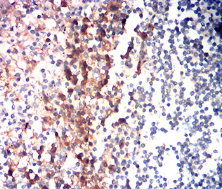

IHC    1/200-1/1000